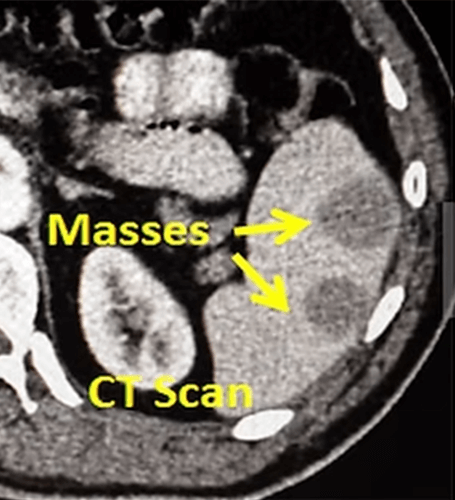

Spleen biopsy is performed under local anesthesia and ultrasound guidance, just like the liver biopsy. Since the risk of bleeding is slightly higher, the spleen capsule should be passed through the needle in one go, the suspicious mass  should be reached. During this time, large vessels in the spleen should be avoided by using color Doppler. Then, with a smaller cutting needle, multiple biopsies are taken from the mass through this needle (coaxial technique). In some cases, there are no separate masses in the spleen, all of the spleen is widely involved (diffuse infiltration). In this case, it is sufficient to take a biopsy from the middle of the spleen. After the biopsies are taken, the inner needle is pulled out and the external needle is checked for bleeding. If there is no bleeding, the external needle is also taken out. If there is obvious bleeding, bleeding is stopped with plugs such as a clot (autologous clot) or coil, glue, and the external needle is then safely withdrawn.